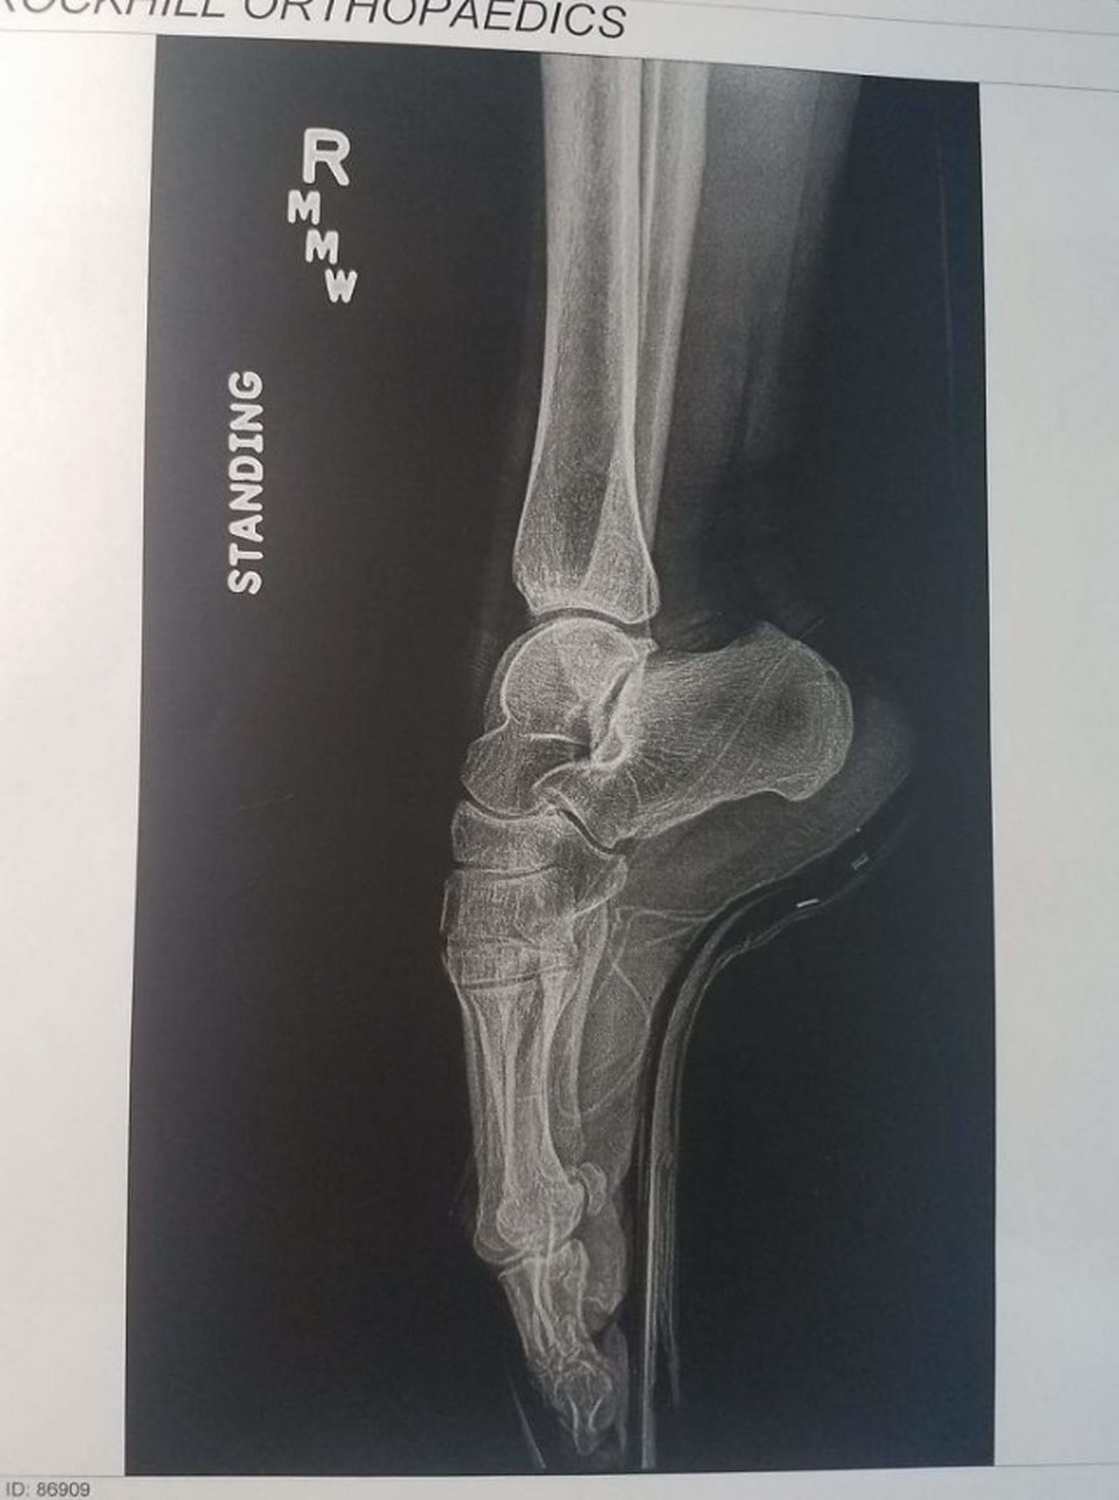

Этот рентгеновский снимок показывает, что при ношении обуви на высоких шпильках вес тела давит на носок ступни, что увеличивает риск травм и вызывает болезни ног